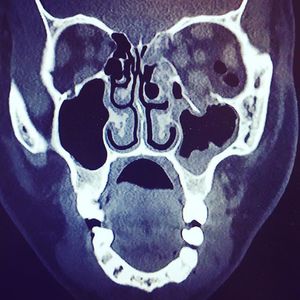

Can you spot the fracture? ๐ต๐ค๐ Orbital floor fracture from a faceplant ๐ฆ๐ The floor of the orbit is the facial bone that holds your eye in place. Fracturing it leads to eye drooping, herniation of periorbital fat into the maxillary sinus, and even entrapment of the inferior rectus muscle, a surgical #emergency. Fortunately this trauma can be repaired with #surgery ! โบ๏ธ๐๐ช